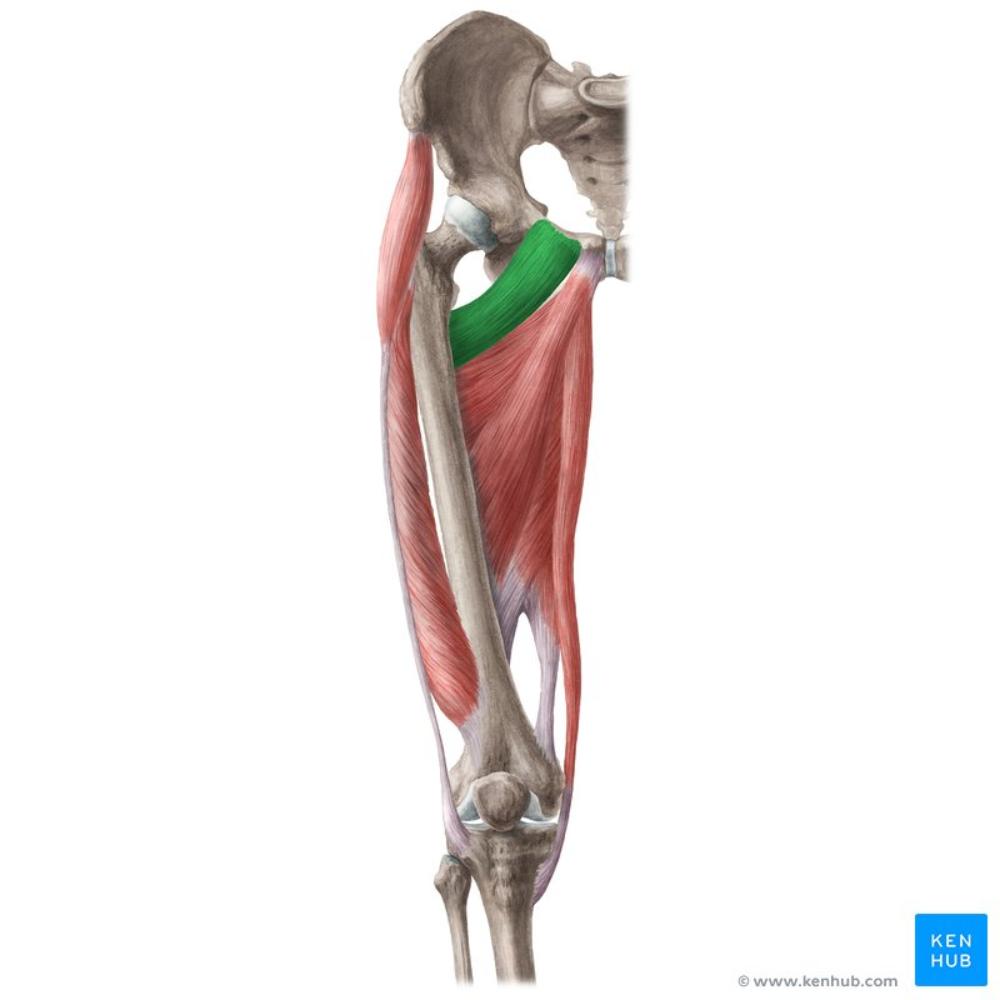

pectineus

O: superior ramus of pubis

I: lesser trochanter

A: flexes thigh, assists in adduction when hip flexed

N: femoral nerve